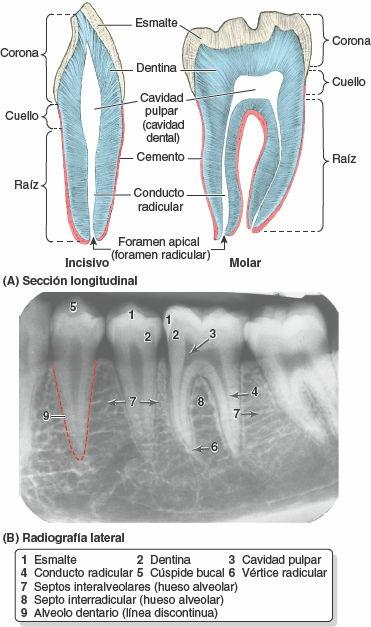

Los dientes se componen de corona, cuello y raíz (fig. 8-82). La corona sobresale de la encía. El cuello se halla entre la corona y la raíz. La raíz está unida al alvéolo dentario por el periodonto (tejido conectivo rodeado de raíces); el número de raíces es variable. La mayor parte del diente está constituida por la dentina, cubierta por el esmalte sobre la corona, y por el cemento sobre la raíz. La cavidad pulpar contiene tejido conectivo, vasos sanguíneos y nervios. El conducto radicular (conducto pulpar) da paso a los nervios y vasos que entran y salen de la cavidad pulpar a través del foramen apical.

Los alvéolos dentarios (figs. 8-81 B y 8-82 B) se hallan en los procesos alveolares del maxilar y la parte alveolar de la mandíbula (fig. 8-80 A). Son las estructuras esqueléticas que experimentan un mayor cambio a lo largo de la vida (fig. 8-81 B). Los alvéolos adyacentes están separados por los septos interalveolares; dentro del alvéolo, las raíces de los dientes que poseen más de una raíz están separadas por los septos interradiculares (figs. 8-81 B y 8-82 B). El hueso del alvéolo posee una fina corteza que está separada de las cortezas labial y lingual adyacentes por una cantidad variable de hueso trabecular. La pared labial del alvéolo es particularmente delgada en los dientes incisivos; en cambio, en los molares, la pared más delgada es la lingual. Por lo tanto, habitualmente se rompe la cara labial para extraer los incisivos, y la cara lingual para extraer los molares.

Las raíces de los dientes están unidas al hueso del alvéolo por una suspensión elástica que forma un tipo especial de articulación fibrosa, denominada sindesmosis dentoalveolar o gonfosis. El periodonto (membrana periodontal) está compuesto por fibras de colágeno que se extienden entre el cemento de la raíz y el periostio del alvéolo. Recibe abundantes terminaciones nerviosas táctiles presorreceptoras, capilares linfáticos y vasos sanguíneos glomerulares, y actúa como un cojinete hidráulico para frenar la presión masticatoria axial. Las terminaciones nerviosas presorreceptoras son sensibles a cambios de presión.